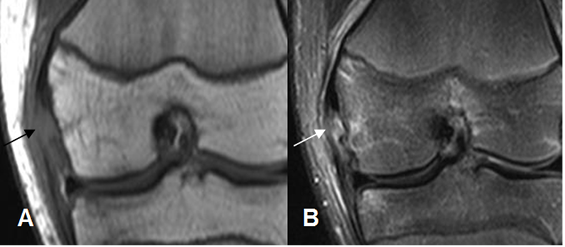

Fig 119. Ruptura del LCM.

A y B: RM coronal en STIR. Solución de continuidad en las fibras del LCM, por ruptura completa.

Fig 120. Ruptura del LCM.

A y B: RM coronal en STIR. Ruptura del LCM en la inserción tibia (A) y en el origen

femoral. (B).